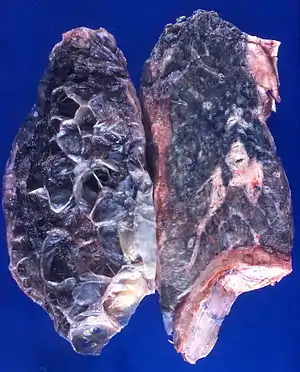

Left lung completely affected by bullae shown in contrast to a normal lung on the right.

Pulmonary emphysema, more usually called emphysema, is characterised by air-filled cavities or spaces, (pneumatoses) in the lung, that can vary in size and may be very large. The spaces are caused by the breakdown of the walls of the alveoli and they replace the spongy lung parenchyma. This reduces the total alveolar surface available for gas exchange leading to a reduction in oxygen supply for the blood.[2] Emphysema usually affects the middle aged or older population. This is because the disease takes time to develop with the effects of smoking, and other risk factors. Alpha-1 antitrypsin deficiency is a genetic risk factor that may lead to the condition presenting earlier.[3]

It is a typical feature of chronic obstructive pulmonary disease (COPD), a type of obstructive lung disease characterized by long-term breathing problems and poor airflow.[4][5] Even without COPD, the finding of pulmonary emphysema on a CT lung scan confers a higher mortality in tobacco smokers.[6] In 2016 in the United States there were 6,977 deaths from emphysema – 2.2 per 100,000 of the population.[7] A study on the effects of tobacco and cannabis smoking showed that a possibly cumulative toxic effect could be a risk factor for developing emphysema, and spontaneous pneumothorax.[8] There is an association between emphysema and osteoporosis.[9]